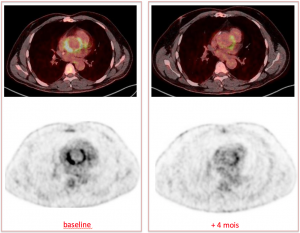

TEP FDG initial: Foyer hypermétabolique hémi-circonférentiel de la portion aortique de la prothèse de Bentall (SUV=17), venant au contact de la valve prothétique.

Contrôle après 4 mois d’antibiothérapie: disparition du foyer hypermétabolique péri aortique pathologique, il persiste un hypermétabolisme modéré circonférentiel au niveau de l’anneau valvulaire prothétique (SUV=4, non pathologique).